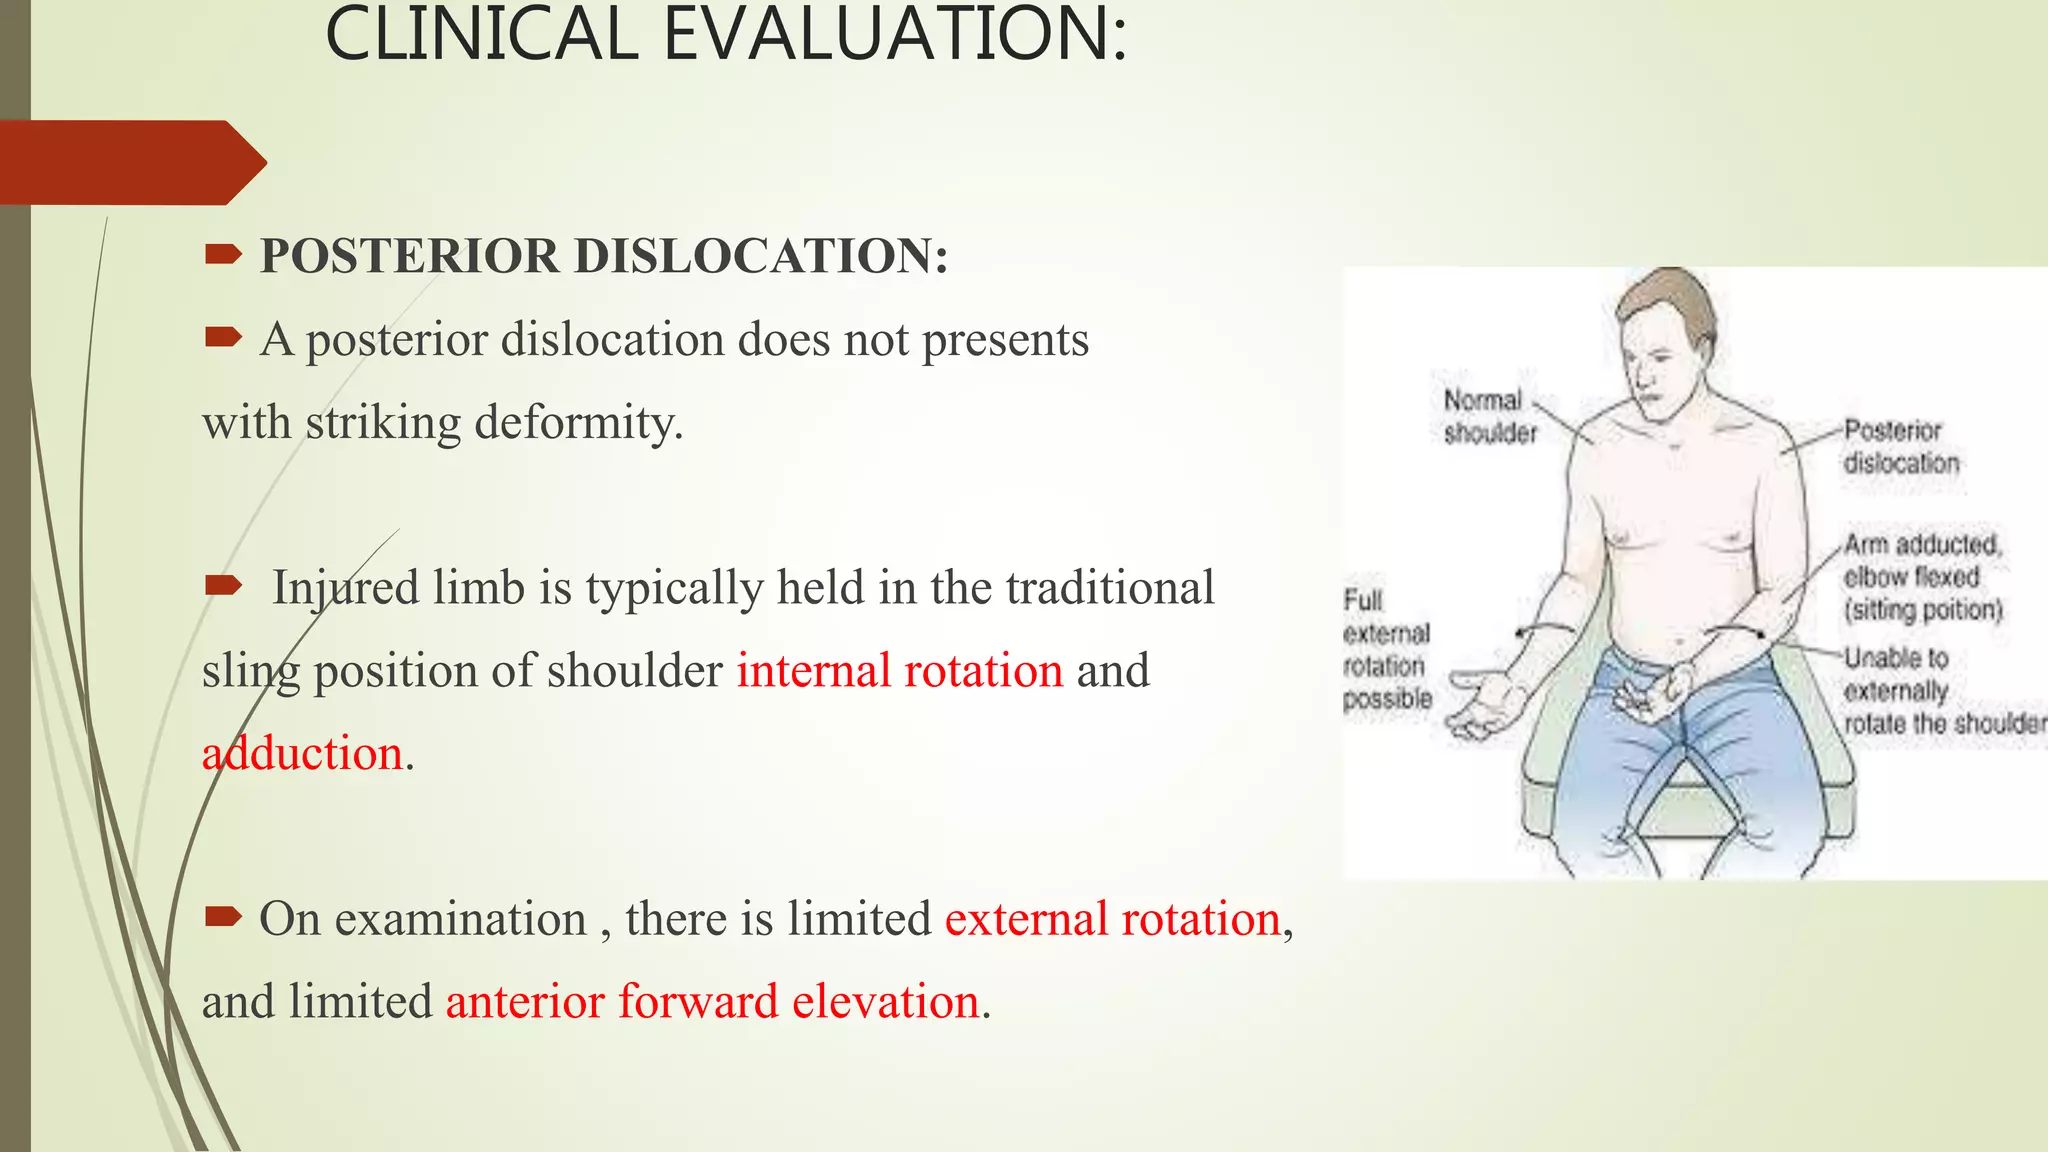

- Clinical evaluation and radiographs are used to diagnose the type of dislocation and assess for complications like fractures.